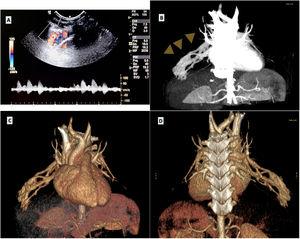

Malformación arteriovenosa pulmonar compleja en un niño de 18 meses

Ricardo Craveiro Costa, Catarina Schrempp Esteves, Inês Marques, Hugo Castro Faria

An Pediatr (Barc). 2024;100:299-300

Acceso a texto completo